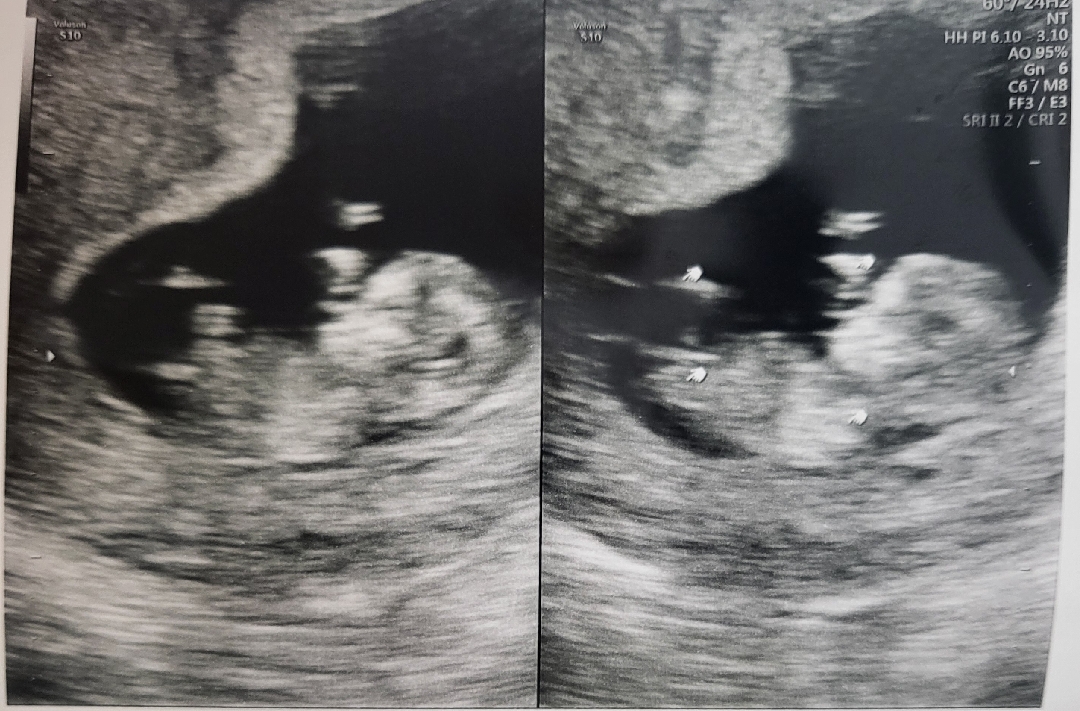

딸이였음하는데 어떻게보이시나용

좀 이르긴한데11주4일입니닷!

아직은없어요ㅠㅠ 혹시각도법으로 볼수있을까해서요ㅎㅎ

이사진으로는 하반신이 안나와있어서 각도법도 어려울거같아요ㅠㅜ 많이 궁금하시겠지만 그래도 쪼금만 더 기다려볼까요 🙂